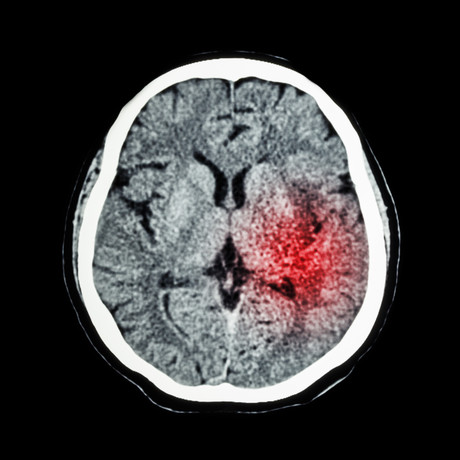

Stroke doubles dementia risk

Having a stroke more than doubles the likelihood of developing dementia, and having a history of stroke increases the risk by around 70%, according to a new global study.

The University of Exeter Medical School in the UK led the study which analysed data on stroke and dementia risk from 3.2 million people across the world. The link between stroke and dementia persisted even after taking into account other dementia risk factors such as blood pressure, diabetes and cardiovascular disease. Their findings give the strongest evidence to date that having a stroke significantly increases the risk of dementia.

Stroke characteristics such as the location and extent of brain damage may help to explain variation in dementia risk observed between studies, and there was some suggestion that dementia risk may be higher for men following stroke.